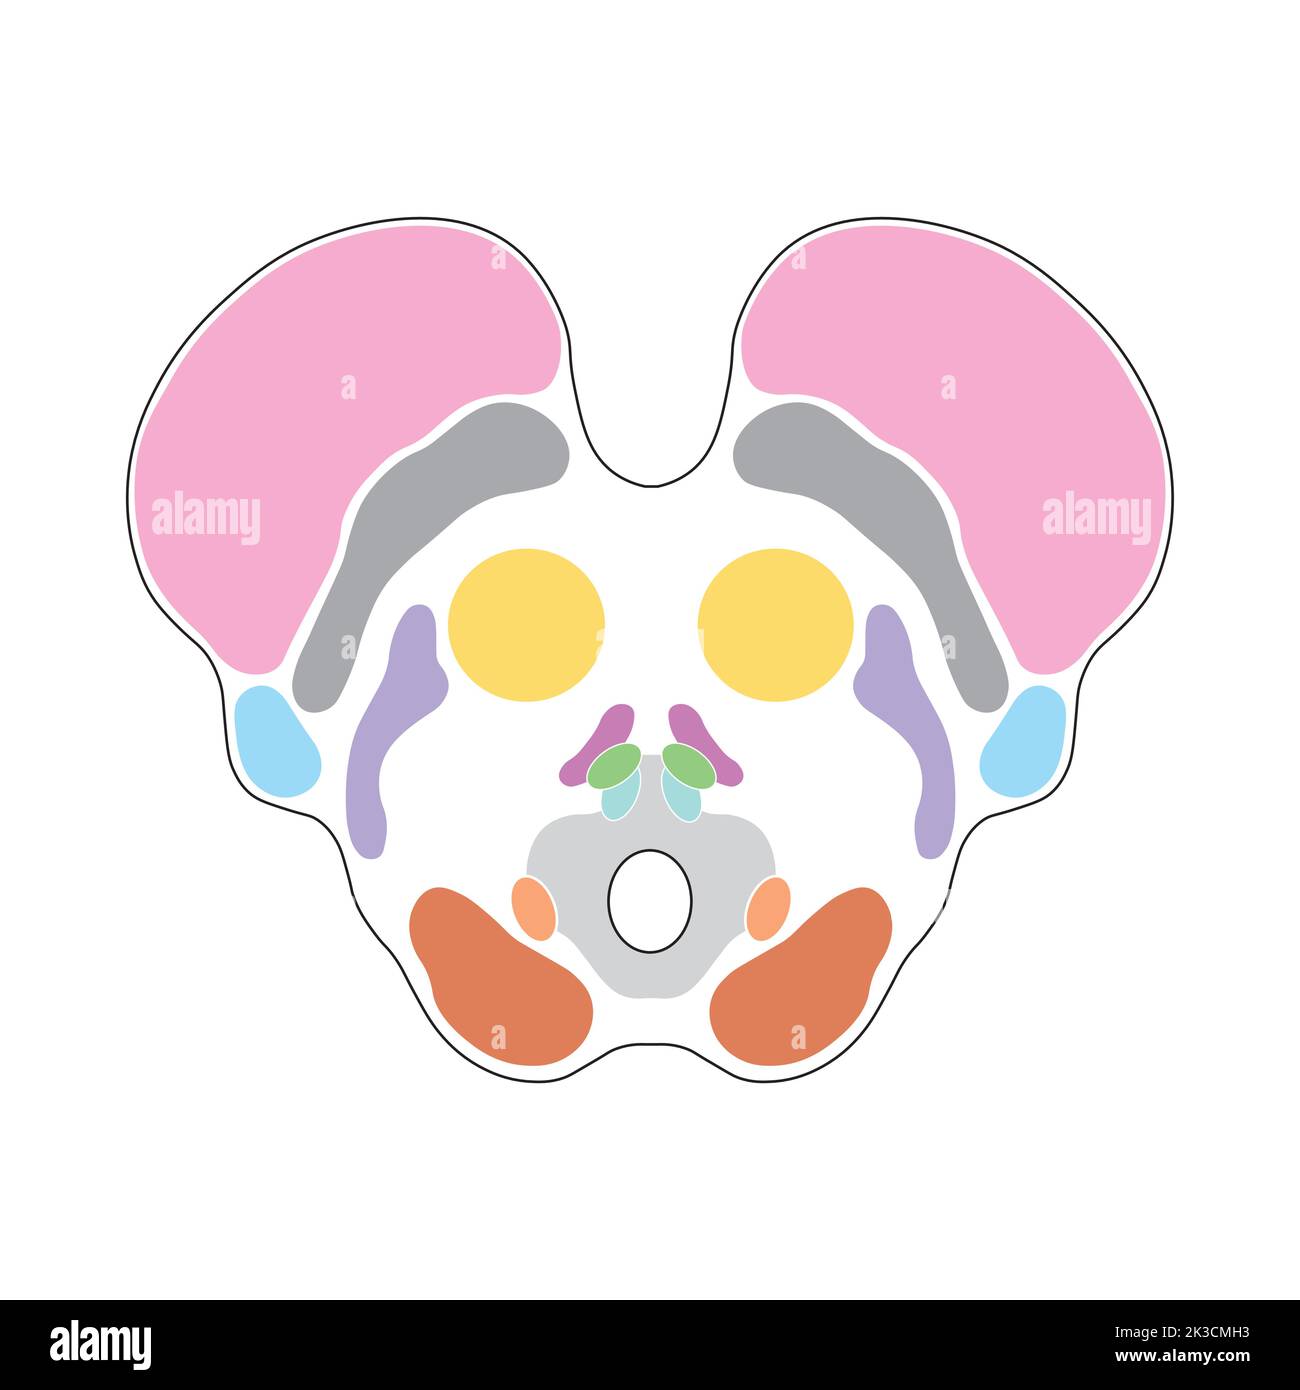

RF2K3CMNG–Wissenschaftliche Gestaltung der Anatomie des Mittelhirns. Axialer Schnitt auf der Ebene des Oberen Kollikulus. Bunte Symbole. Vektorgrafik.

RF2K3CMHJ–Wissenschaftliche Gestaltung der Anatomie des Mittelhirns. Axialer Schnitt auf der Ebene des Oberen Kollikulus. Bunte Symbole. Vektorgrafik.

RF2K3CMH3–Wissenschaftliche Gestaltung der Anatomie des Mittelhirns. Axialer Schnitt auf der Ebene des Oberen Kollikulus. Bunte Symbole. Vektorgrafik.